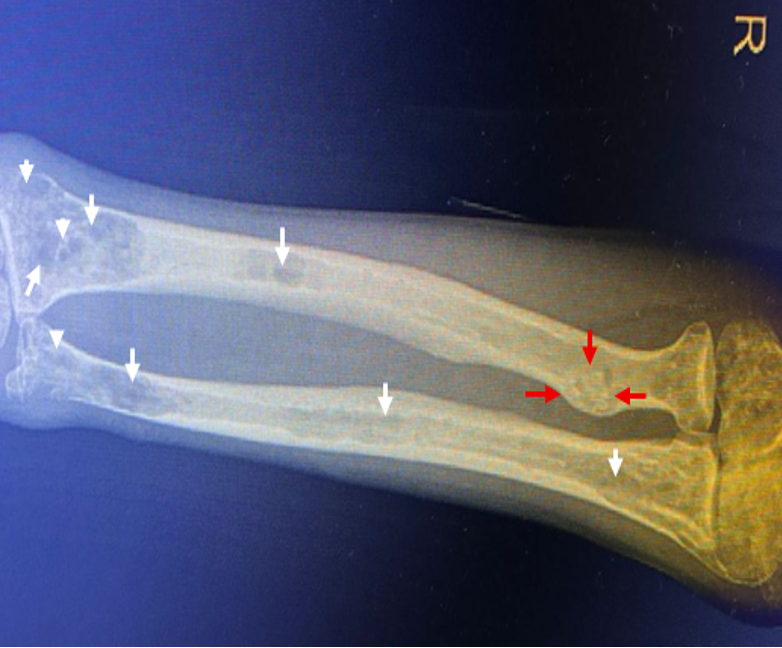

Briefly highlighting some unseen evidence of two comorbid COVID-19 patients

Abdullah, Muhammad Salman, Sher Ali, Riaz Muhammad, Aiman Waheed, Muddasir Khan, Sana Ullah, Carlos Augusto Fernandes de Oliveira